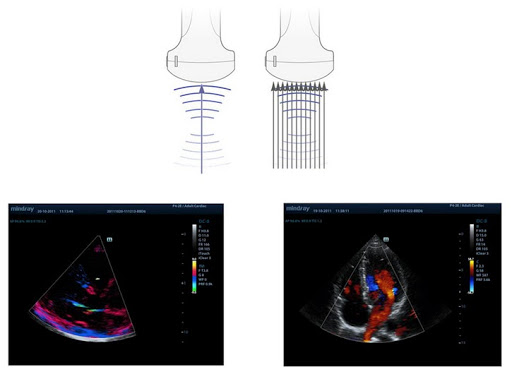

Формирование мульти-луча

Увеличение скорости обработки сигнала от одного луча до 12 раз позволяет достигать превосходного временного разрешения и более высокой частоты кадров.